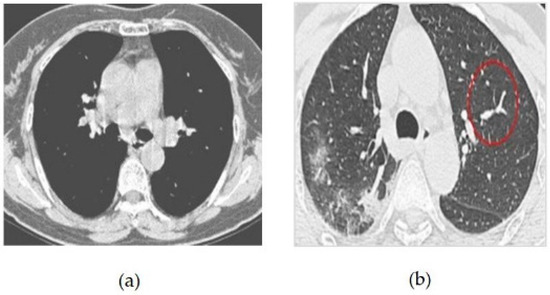

The CT image dataset contains approximately 349 CT images from 216 patients with coronavirus and 397 patients without coronavirus. The images were collected from hospitals that treat both coronavirus and non-coronavirus patients, but only the positive and negative cases for coronavirus were included in the dataset [13,14]. Some of the samples of coronavirus images in both positive and negative classes are given in Figure 4. The features of the dataset are as follows:

Figure 4. (a) COVID-19 Negative (COVID-19 images collection dataset) (b) COVID-19 Positive (COVID-19 images collection dataset).